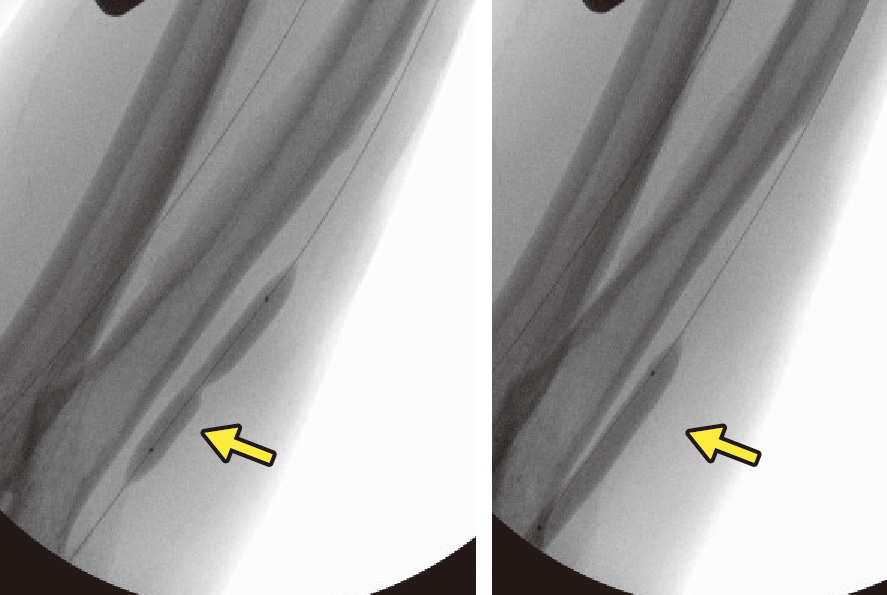

バスキュラーアクセスに狭窄をきたす場合には,脱血不良や静脈圧上昇などがみられ,最終的にバスキュラーアクセスを使用することができなくなる.このため,外科的治療以外に,冠動脈と同様にバルーンで拡張する治療 (percutaneous transluminal angioplasty: PTA) が行われている (図11).